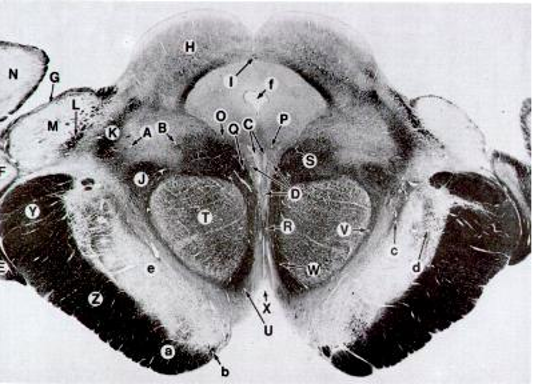

Rostral Midbrain Cross section

<p>Z</p>

Z

Corticospinal Tract

2

New cards

<p>T</p>

T

Red Nucleus

3

<p>H</p>

H

Superior Colliculi

4

<p>D</p>

D

CrN. III Nucleus

5

<p>C</p>

C

6

<p>e</p>

e

Substancia Nigra

7

<p>f</p>

f

Cerebral Aquaduct